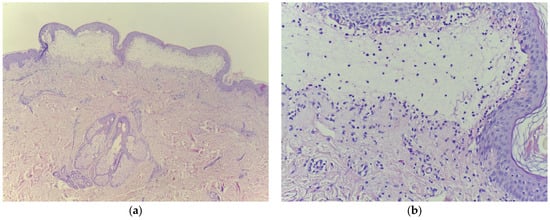

2. Bullous Pemphigoid Overlapping Psoriasis Vulgaris: A Rare Case Report